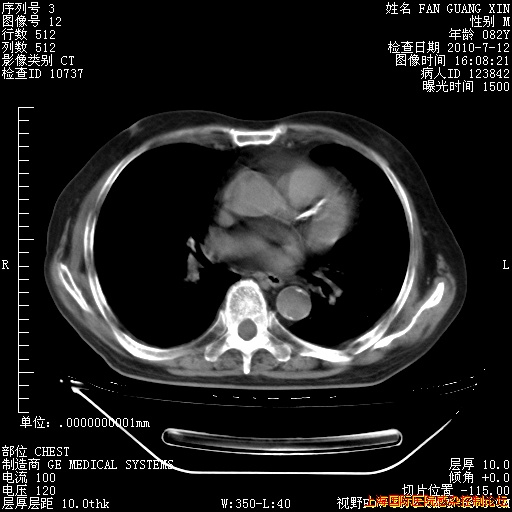

今天复查CT

今天CT

整整相隔30天的肺部CT好像有所好转啊。甲强龙减量第3天,需要观察体温。

海管,自昨日你和我通完话后,不知您岳父消化道症状有无缓解?体温怎样?阅读7.12日胸部ct,个人认为目前激素治疗是有效的,甲强龙减量是适宜的。因在抗痨治疗,需密切观察肝功、肾功能和血常规。不过,老年、长期住院和大量使用激素,很担心菌群失调发生